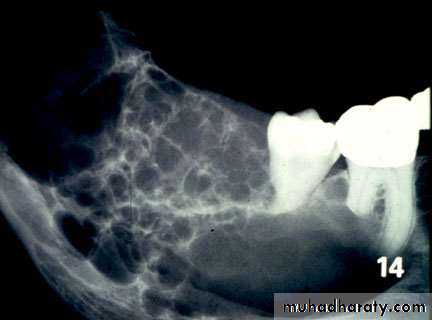

Multilocular radioluscency honey comb or soap bubble appearance.-In unicystic ameloblastoma unilocular radioluscency.

Thinning and expansion of cortical plate. Thinning of lamina dura.

Truncation /Amputation of roots